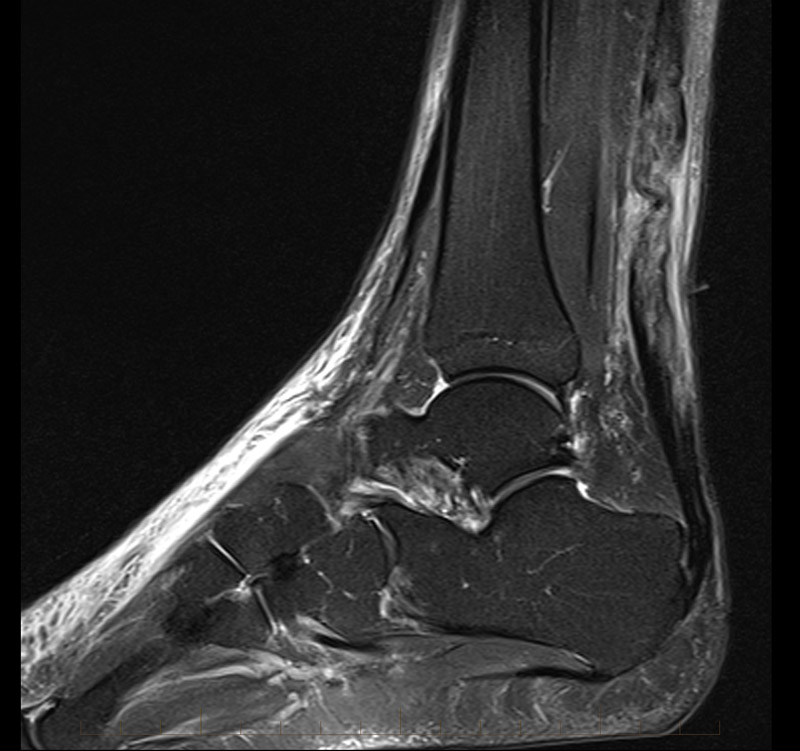

Mri Shows Wear And Tear . I had my right knee x rayed and also a scan which revealed minor wear and tear. The breakdown or wear and tear of knee structures, often seen in aging or overuse. Mri reports often describe various types of lesions or abnormalities found within the body. Common terms used to describe these findings include: The scan cannot distinguish between natural, painless wear and tear and painful degeneration in the spinal column. Excess fluid in the knee joint, often indicating inflammation or injury. White matter lesions are one of the most common incidental findings on brain scans. Hi, i have wear & tear in my lower back & right knee. This is usually the result of normal ‘wear and tear,’ over time, to the smallest blood vessels in the brain, leading to either microscopic ruptures or blockages of those end vessels, and scarring of the. To see any tears or other damage to your muscles and tendons and possibly ligaments, he or she will need to order an mri scan, also called magnetic resonance imaging. An abnormal growth or lump within. These appear as bright areas or white matter ‘hyperintensities’ on some brain mri scans. Tears can be partial or complete. A rip or split in any of the knee structures, commonly involving the meniscus or ligaments. In older patients, because of the common and often asymptomatic “wear and tear” that is common in these patients, mri’s often overemphasize the importance of common.

Hi, i have wear & tear in my lower back & right knee. The breakdown or wear and tear of knee structures, often seen in aging or overuse. Tears can be partial or complete. In older patients, because of the common and often asymptomatic “wear and tear” that is common in these patients, mri’s often overemphasize the importance of common. The scan cannot distinguish between natural, painless wear and tear and painful degeneration in the spinal column. This is usually the result of normal ‘wear and tear,’ over time, to the smallest blood vessels in the brain, leading to either microscopic ruptures or blockages of those end vessels, and scarring of the. A rip or split in any of the knee structures, commonly involving the meniscus or ligaments. To see any tears or other damage to your muscles and tendons and possibly ligaments, he or she will need to order an mri scan, also called magnetic resonance imaging. White matter lesions are one of the most common incidental findings on brain scans. Common terms used to describe these findings include: